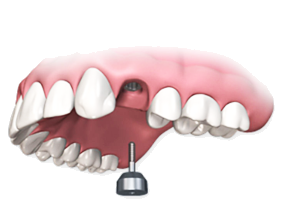

Восстановление зуба на имплантате

Имплантология - это восстановление утраченных зубов методом вживления в челюсть титановых аналогов корней зубов.

Установка и приживление имплантата

Хирург вживляет в кость имплантат из титана.

Операция занимает около 20 минут. Вместе с подготовкой, анестезией и наложением швов около 1 часа. Интеграция имплантата занимает от 2-х до 6-ти месяцев.

Устанавливается формирователь десны

Через несколько месяцев, после приживления имплантата,

на него устанавливается титановый колпачек. Он готовит десну к появлению в этом месте нового зуба.

Установка коронки

Откручиваем формирователь десны и устанавливаем индивидуально спроектированный абатмент и коронку. В результате зуб неотличим от настоящего и имеет надежный корень в виде срощенного с костью титанового имплантата.